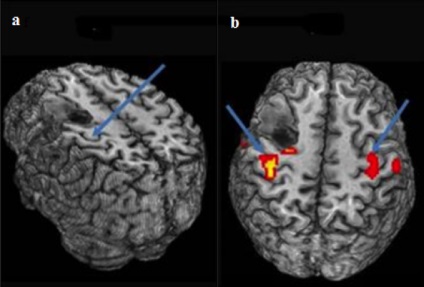

In practica BOLD fMRI utilizat pentru rezecția preoperator planificarea (indepartarea) a tumorilor, diagnosticul malformațiilor vasculare, în timpul operațiilor în forme severe de epilepsie si alte leziuni cerebrale. In timpul creier chirurgie este important cât mai precis posibil pentru a elimina zona afectată, în același timp, evitând deteriorarea inutile funtsionalnost adiacente importante părți ale creierului.

Metoda este foarte eficientă în studiul bolilor degenerative, cum ar fi bolile Parkinson și Alzheimer, mai ales în stadii incipiente. El nu folosește radiații ionizante și contrast mass-media, în plus, este non-invaziva. Prin urmare, acesta poate fi considerat suficient de sigur pentru pacienții care au nevoie pe termen lung și examene regulate fMRI. FMRI pot fi folosite pentru a studia mecanismele de crize epileptice și pentru a evita eliminarea cortexului funcțional la pacienții cu epilepsie refractară a lobului frontal. Monitorizarea recuperarea creierului dupa un accident vascular cerebral, studiul influenței drogurilor sau a unei alte terapii, monitoriza și controla tratamentul bolilor psihice - aceasta nu este o listă completă a posibilei utilizări a fMRI. În plus, există fMRI de odihnă, în care rețeaua de prelucrare a datelor complexe ne permite să vedem creierul funcționează în repaus.